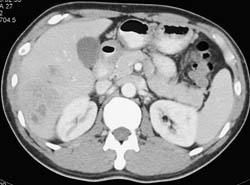

Budd-Chiari Syndrome